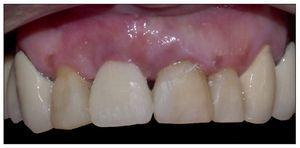

Figura 2. Ausencia total de tabla vestibular en relación con la pieza 8.

Figura 9. Ausencia total de tabla ósea vestibular en relación con la pieza 9.